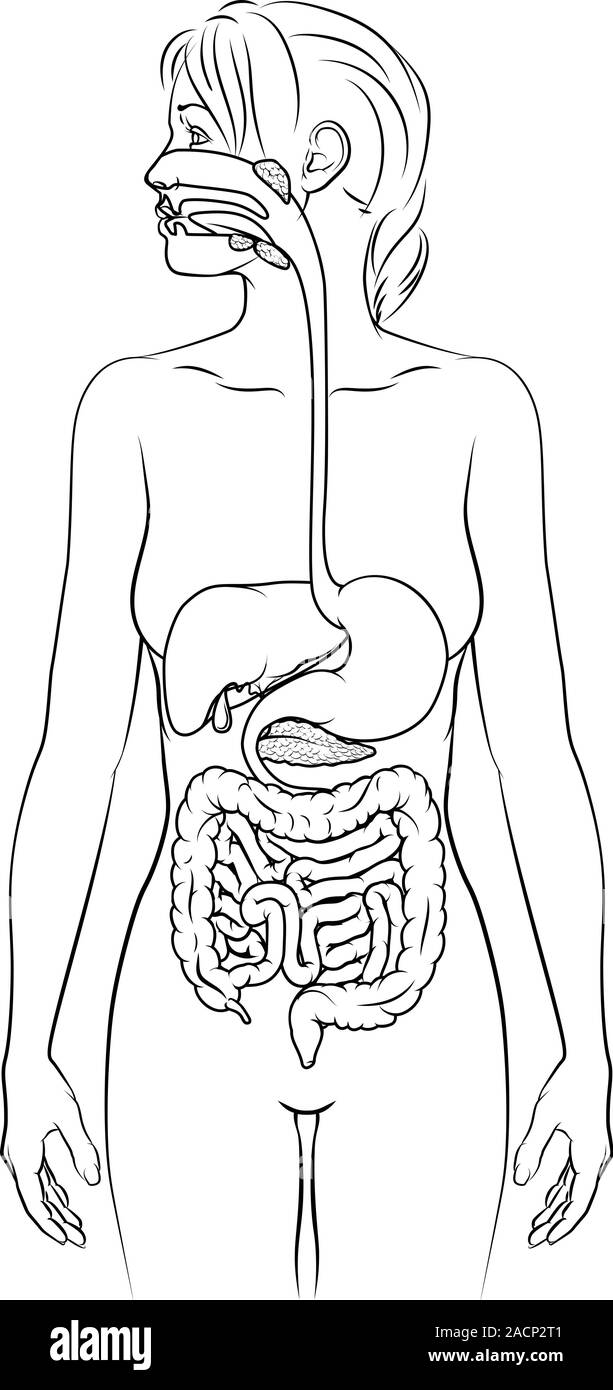

Système digestif humain Femme Schéma anatomique Illustration de Vecteurhttps://www.alamyimages.fr/image-license-details/?v=1https://www.alamyimages.fr/systeme-digestif-humain-femme-schema-anatomique-image334858049.html

Système digestif humain Femme Schéma anatomique Illustration de Vecteurhttps://www.alamyimages.fr/image-license-details/?v=1https://www.alamyimages.fr/systeme-digestif-humain-femme-schema-anatomique-image334858049.htmlRF2ACP2T1–Système digestif humain Femme Schéma anatomique